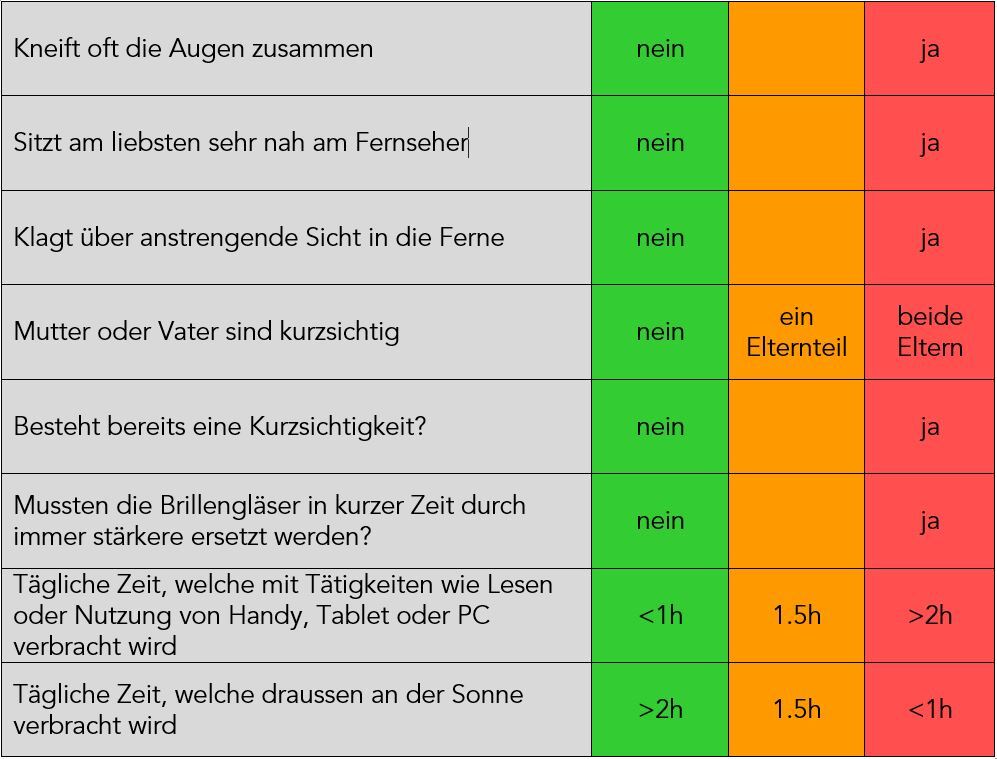

Selbstcheck Kurzsichtigkeit

Beantworten Sie folgenden Fragen für Ihr Kind bzw. für sich selbst, wenn Sie persönlich betroffen sind:

Sind zwei oder mehr der Antworten im orangen oder roten Bereich? Dann macht eine eingehende Abklärung durch unsere Optometristen Sinn. Melden Sie sich online oder per Telefon 033 222 54 22 für eine kostenlose Erstberatung an.